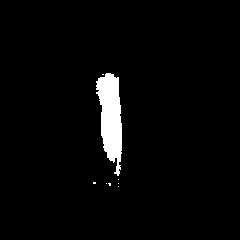

Glioma is a prevalent brain tumor that poses a significant health risk to individuals. Accurate segmentation of brain tumor is essential for clinical diagnosis and treatment. The Segment Anything Model(SAM), released by Meta AI, is a fundamental model in image segmentation and has excellent zero-sample generalization capabilities. Thus, it is interesting to apply SAM to the task of brain tumor segmentation. In this study, we evaluated the performance of SAM on brain tumor segmentation and found that without any model fine-tuning, there is still a gap between SAM and the current state-of-the-art(SOTA) model.